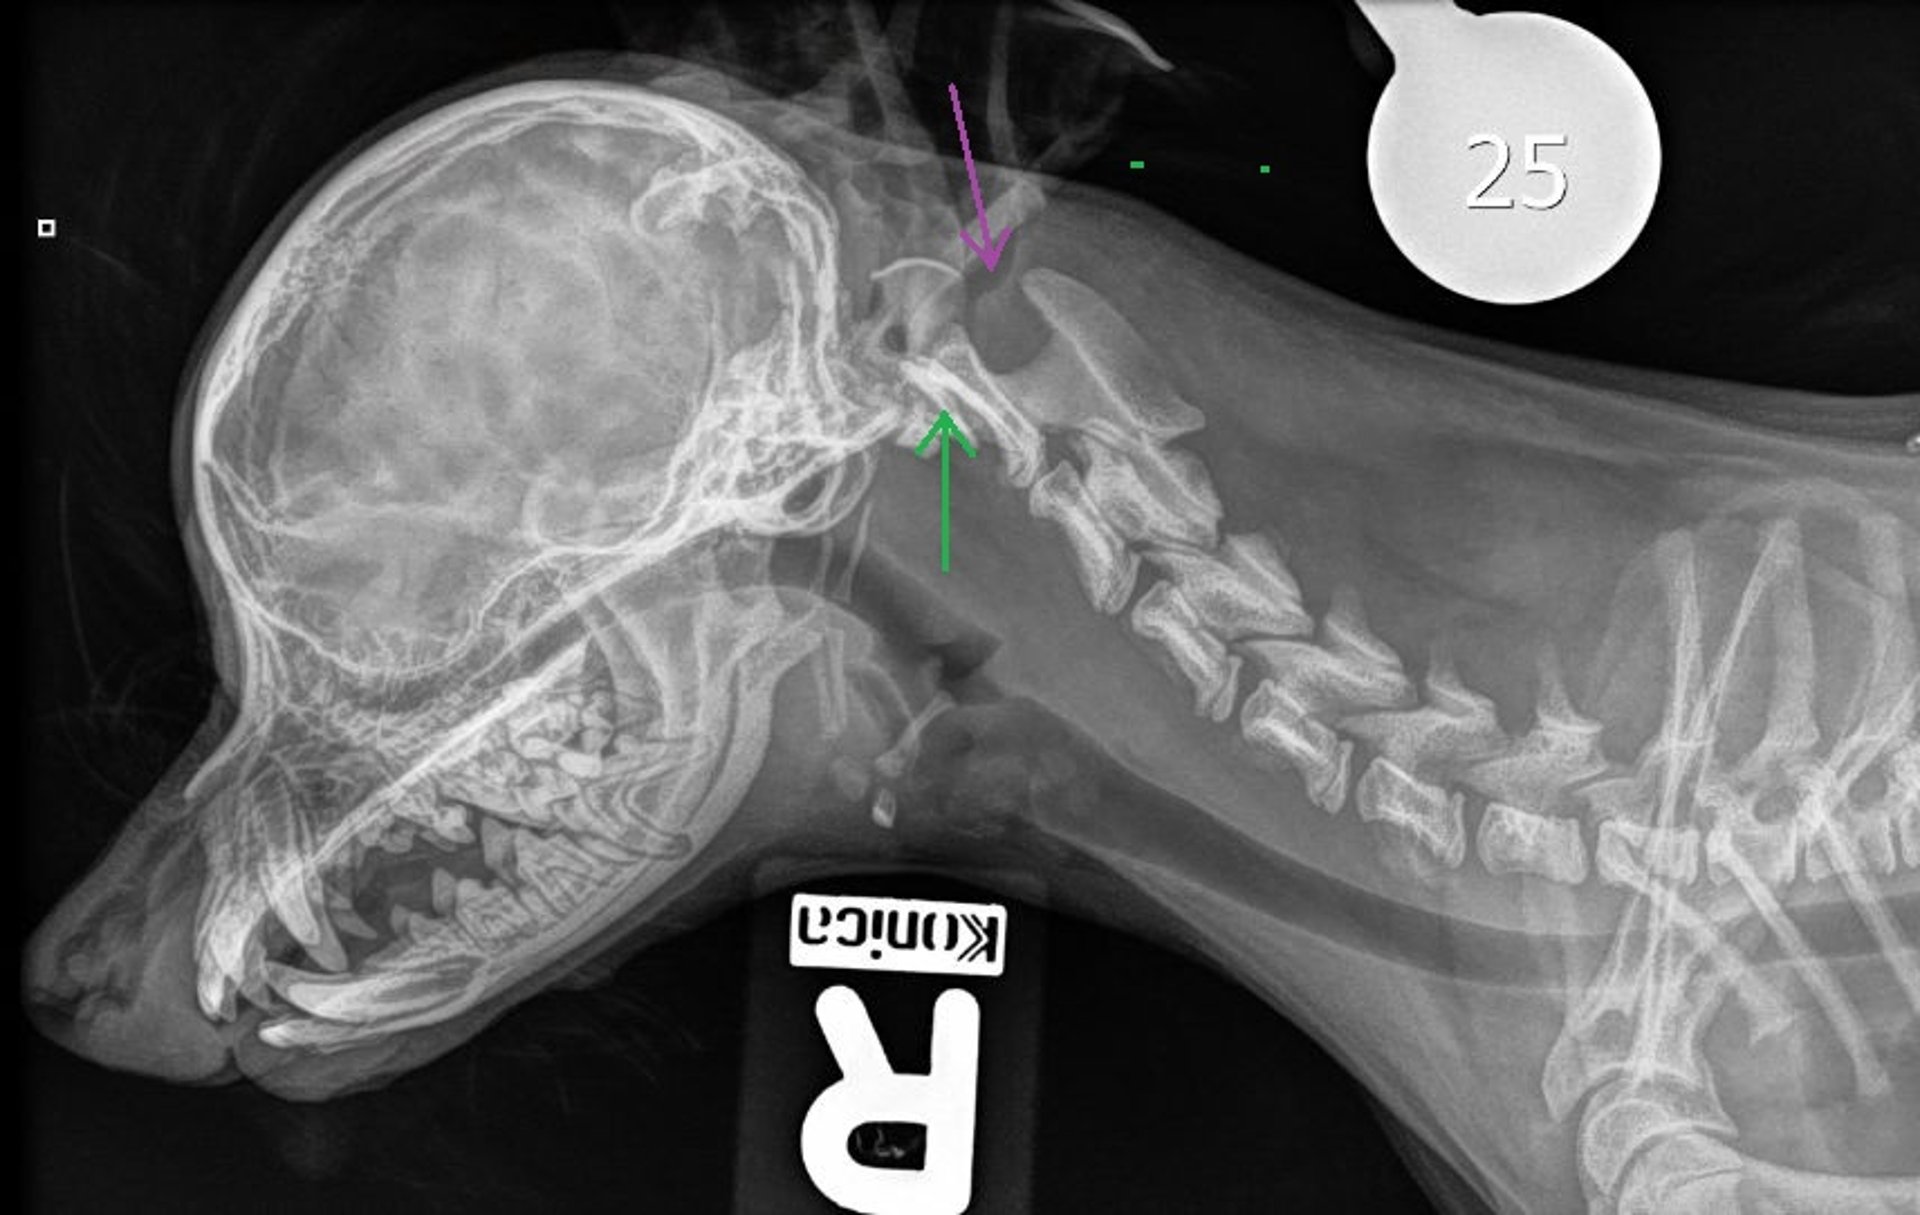

Lateral radiograph of the cranium and cervical spine in a dog with atlantoaxial subluxation. Note the absent/aplastic dens (green arrow) and caudal dorsal displacement of C2 compared to C1 (purple arrow), with an increased angle between the dorsal spinous process of C2 and the dorsal lamina of C1.

Courtesy of Dr. Genesis Lopez Bonilla.